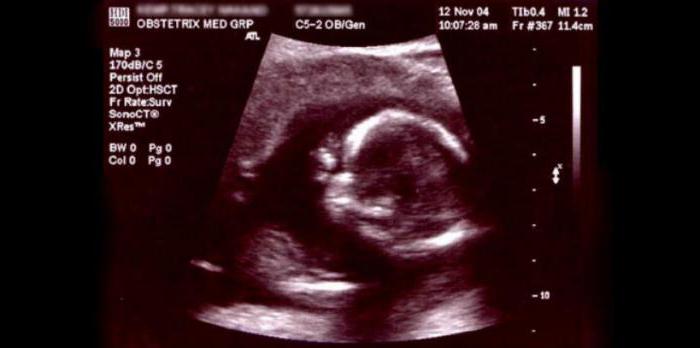

Первое УЗИ делают обычно на сроке от 12 до 13 недель. Оно позволяет выявить начальные маркеры угрозы синдрома Дауна. Второе УЗИ осуществляется на 20-22 неделе, третье — незадолго до родов. Обычно на них опытный врач с вероятностью до 70-80% может сказать о наличии хромосомных отклонений.

На 12-недельном сроке беременности скрининговое ультразвуковое обследование делается с целью получения данных о правильности развития плода, наличии/отсутствии каких-либо пороков или хромосомных аномалий. Благодаря дополнительно проводимому на сроке 12 недель генетическому обследованию в виде сдачи крови, каждая беременная женщина сможет получить наиболее достоверные сведения о возможных пороках развития ребёнка.

Кроме того скрининг-УЗИ делают впервые именно на сроке 12 недель с целью установки гестационного возраста плода. В этот период УЗИ показывает максимально точный результат, который станет для доктора ориентиром на весь срок беременности.

При проведении скрининг УЗИ в 12 недель беременности особое внимание уделяется головному мозгу, который к данному сроку должен иметь два полушария. Кроме того процедура позволяет врачу проанализировать воротниковую область и установить ее толщину, которая показывает, есть ли риск возникновения болезни Дауна. Если показатели толщины не соответствуют норме (в пределах от 2 до 3 мм), а превышают ее, то врач будет подозревать у плода наличие хромосомных аномалий. В этом случае усиливается контроль над состоянием будущей мамы и тем, как развивается ребенок, и повторно делается скрининг УЗИ через 2 недели.